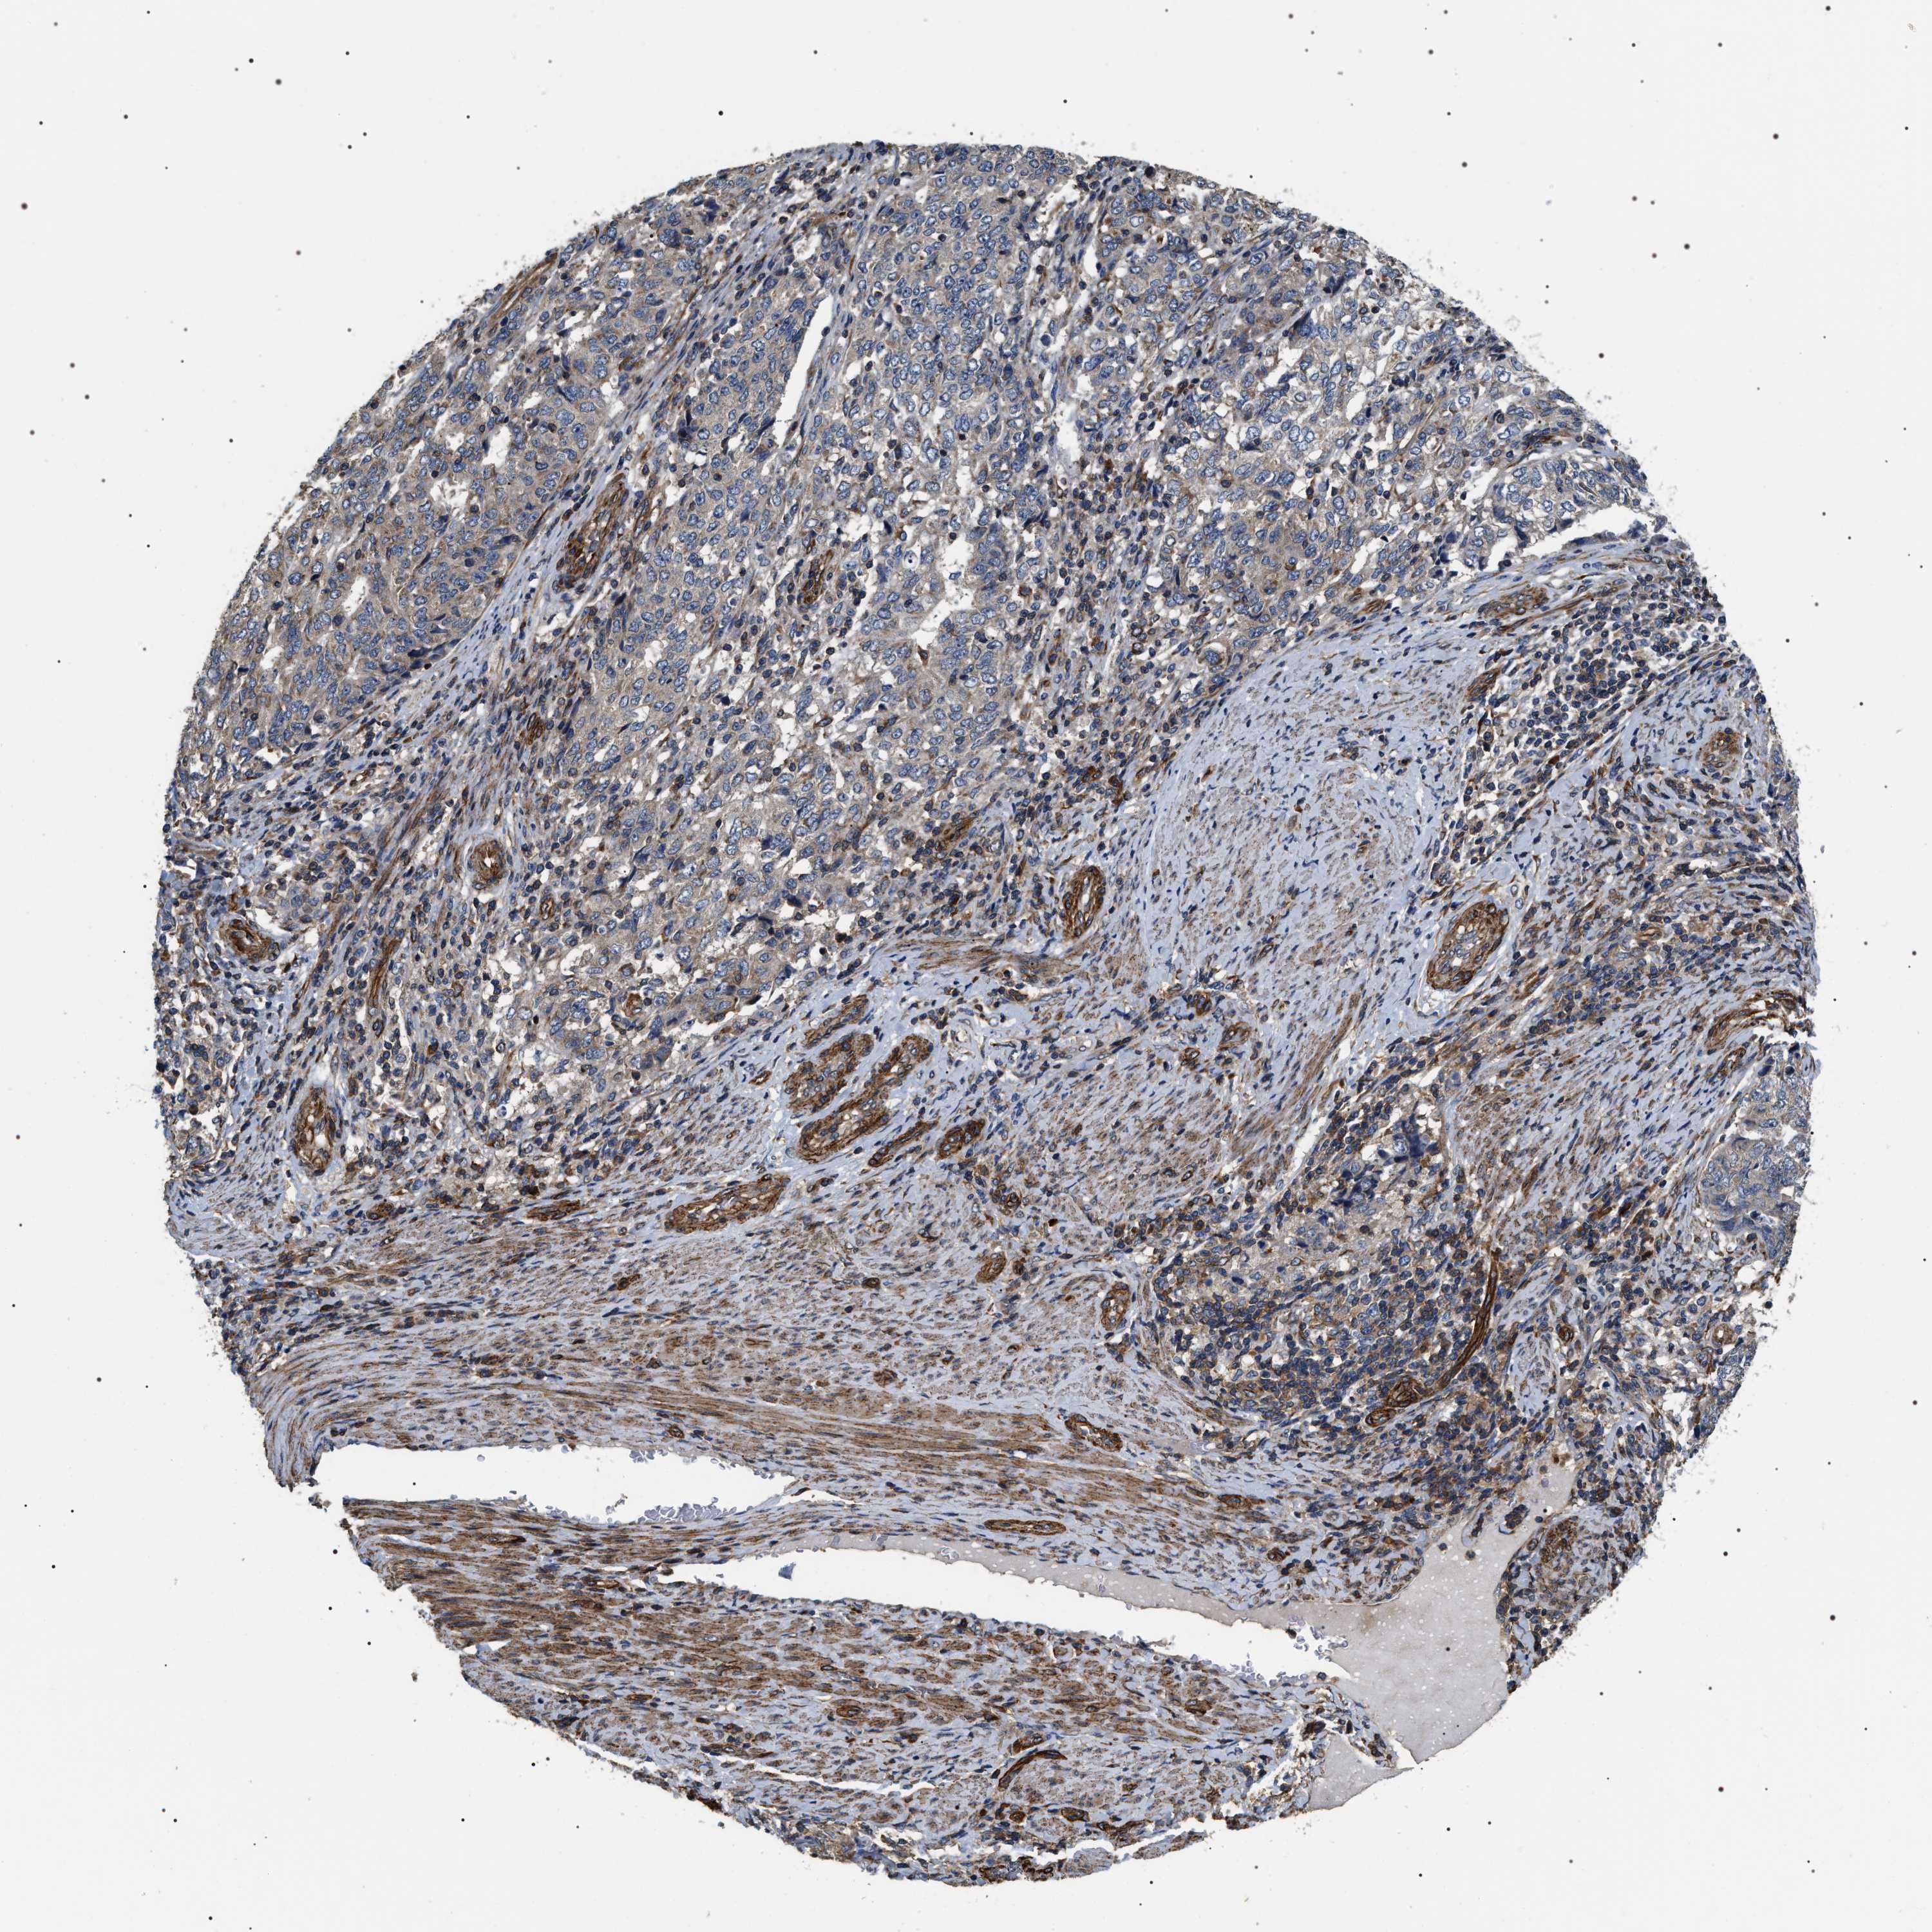

ENDOMETRIAL CANCER - Protein expressioni

A mouse-over function shows sample information and annotation data. Click on an image to view it in a full screen mode. Samples can be filtered based on level of antibody staining by selecting one or several of the following categories: high, medium, low and not detected. The assay and annotation is described here.

Note that samples used for immunohistochemistry by the Human Protein Atlas do not correspond to samples in the TCGA dataset.

Antibody stainingi

Antibody staining in the annotated cell types in the current human tissue is reported as not detected, low, medium, or high, based on conventional immunohistochemistry profiling in selected tissues. This score is based on the combination of the staining intensity and fraction of stained cells.

Each image is clickable and will lead to virtual microscopy that enables deeper exploration of all samples and also displays staining intensity scores, fraction scores and subcellular localization as well as patient and tissue information for each sample.

Antibody HPA020386

Staining

High

Medium

Low

Not detected

Intensity

Strong

Moderate

Weak

Negative

Quantity

>75%

75%-25%

<25%

None

Location

Nuclear

Cytoplasmic/membranous

Cytoplasmic/membranous,nuclear

Adenocarcinoma, NOS

Adenoma, NOS